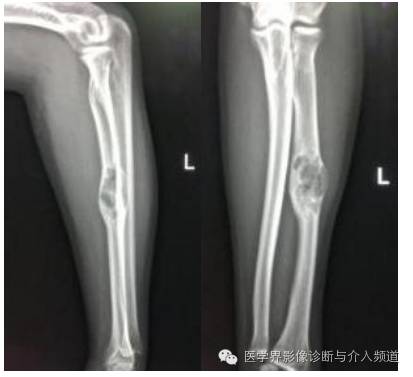

DR:

X线:好发于长骨干骺端,60%-75%见于股骨上端、椎体及附件。跟骨、耻骨、锁骨和掌骨等皆可发病。表现为膨胀性囊状透亮区,与正常骨界面清楚并有硬化边,病灶可位于骨干中央,也可偏心生长。膨胀显著可有菲薄骨壳。囊内有或粗或细的骨小梁状分隔和骨嵴,使病变呈皂泡状外观。病灶可横向扩张,也可沿骨长轴生长。发生在脊椎者,可有长骨病灶的特点,当发生压缩性骨折后则失去特点。如果同时发现附件膨胀性病变,可助于诊断。